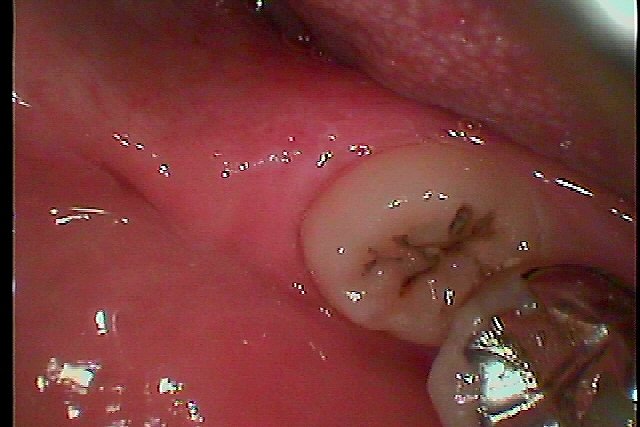

そうすると、左下も変な味がするとのこと

風をかけると歯茎もめくれます

まだ32歳ですが周囲炎にて骨吸収も激しいです

麻酔をかけると多くの排膿が認められました